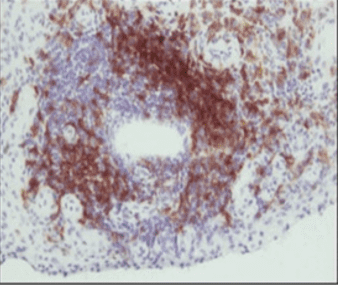

The joints of patients with inflammatory arthritis (IA) show a complex microenvironment of neoangiogenesis, immune cell and fibroblast activation leading to inflammation and joint destruction. T cells play a key role in the pathogenesis of both Rheumatoid Arthritis and Psoriatic arthritis, with differential T cell populations associated with both diseases. It has now emerged that T cell subsets can exhibit functional plasticity, particularly, making it difficult to identify discrete T cell subsets on the basis of their cytokine production. Th17 cells appear to be particularly unstable under inflammatory conditions and can become so-called ex-Th17 cells or nonclassical Th1 cells, which start to produce IFN-γ with the eventual loss of IL-17 expression. Interestingly, we have shown enrichment of polyfunctional Th1, Th17 and Ex-Th17 cells in the periphery and synovial fluid of patients with RA and PsA. In addition, the frequency of polyfunctional T cells are associated with disease activity and response to therapy, suggesting they play a key pathogenic role in disease. Regulatory T cells (Tregs) represent an important peripheral tolerance mechanism that serves to prevent autoimmunity, but fails to constrain inflammation in autoimmune diseases such as RA and PsA. Several studies examining Treg phenotype have reported a decrease in the frequency in peripheral blood of patients with RA/PsA compared with healthy control (HCs), however, studies have also demonstrated enrichment of Tregs at the site of inflammation. However, they have reduced suppressive function thus allowing pathogenic polyfunctional CD161+ cells to further potentiate inflammation. In this study, we investigated the regulation of effector T cells taken from the RA SF by Tregs. The reduced suppression was in part mediated by the CD161+ Th cells, which exhibited enhanced pathogenicity which were resistant to Treg suppression.

In Rheumatology Reproductive Medicine clinic, RA and PsA patients wishing to achieve pregnancy are assessed when they present with active arthritis and intervention is designed to induce remission before conception. Patients are then followed and closely monitored during pregnancy and post-partum to assess disease activity and possible flare. Studies have shown increased frequency and function of Treg cells that are protective in RA patients who are pregnant, however little is known about polyfunctional T cells.